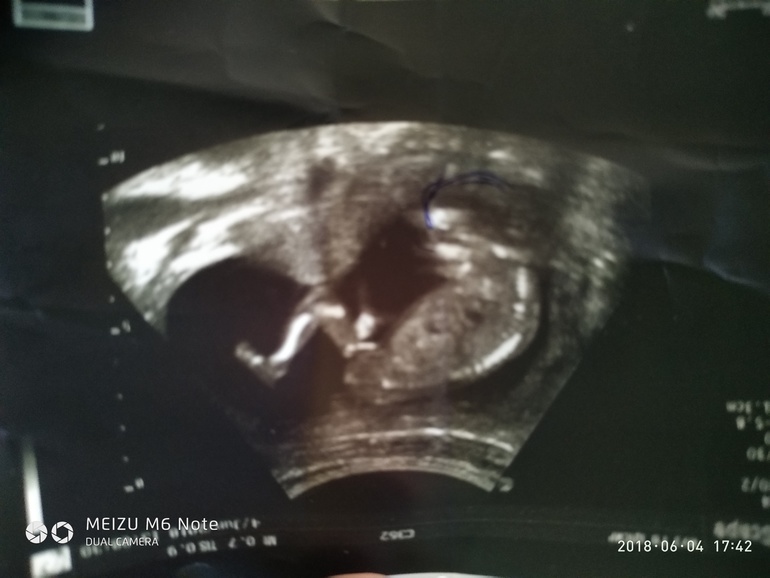

16 недель

Наконец собрала сумку в роддом! 1 скрининг